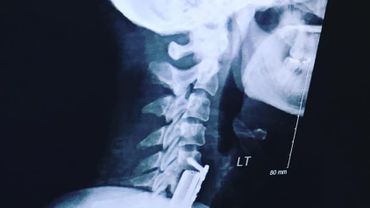

A 46 year old Kentucky drummer. Playing for 43 years injured by a major spinal cord injury & 4 years post spinal fusion may have a second. I’m still drumming!